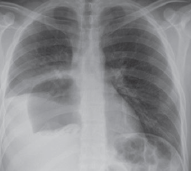

HIDATIDOSIS PULMONAR: HALLAZGOS Y TRATAMIENTO QUIRÚRGICO EN QUISTES COMPLICADOS VERSUS NO COMPLICADOS

Introducción: La hidatidosis humana es una zoonosis prevalente en nuestro medio, causada principalmente por el parásito Echinococcus granulosus. Las complicaciones más frecuentes en el pulmón son la rotura y la infección del quiste.

Resultados: Total 364 episodios de QHP, complicados 179 (49,2%) versus no complicados 185 (50,8%). Edad promedio 36,4±18,9 versus 32,4±19,1 años, hombres 114 (63,7%) versus 107 (57,8%), respectivamente. Se encontró diferencia estadísticamente significativa en: sintomatología tos 147 (82,1%) versus 120 (64,9%), hemoptisis 93 (52,0%) versus 45 (24,3%), respectivamente; QHP derecho 115 (64,2%) versus 99 (53,5%), respectivamente; cirugía conservadora 139 (77,7%) versus 167 (90,3%), reoperaciones 22 (12,3%) versus 8 (4,3%), respectivamente; morbilidad 47 (26,3%) versus 30 (16,2%), mortalidad 6 (3,4%) versus 0 (0%), estadía hospitalaria postoperatoria promedio 16,1±14,3 versus 10,7±7,7 días, recidivas 15 (8,4%) versus 13 (7,0%), respectivamente.